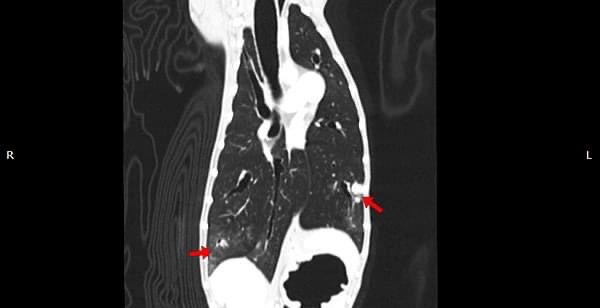

狗狗 鼻腔腫瘤 惡性上皮癌

鼻腔腫瘤的診斷需要仰賴電腦斷層掃瞄定位病灶處,同時使用鼻腔內視鏡探查、採樣才能確診,同時有這兩項設備的醫院並不多,所以臨床上並不是那麼容易確診。狗狗的慢性鼻炎維持3-4個月,越來越嚴重,他院轉診至築心,經由內視鏡+電腦斷層確認為鼻腔上皮癌,而且由於病程時間長,已經轉移至胸腔,代表壽命不長了,至少家人心中有個答案,有心理準備陪狗狗最後一段路。